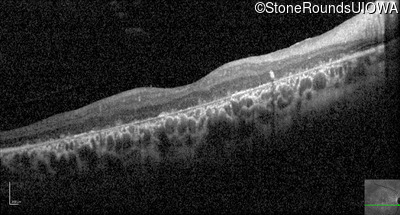

Optical Coherence Tomography - Right - 10/125 -2 sc

Exemplar / OCT Stack